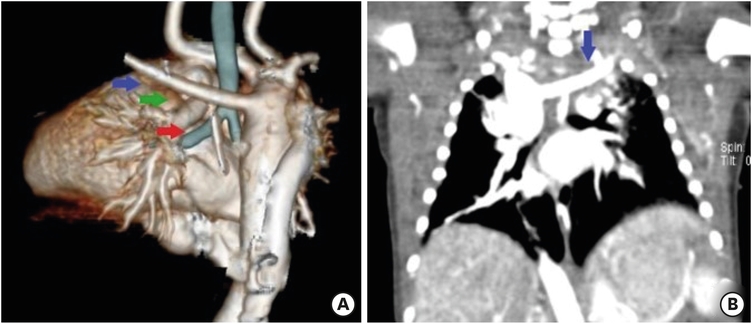

Fig. 3

Pulmonary 3D CT angiography.

(A) Pulmonary 3D CT angiography showing right-sided aortic arch (green arrow), hypoplastic superior vena cava, prominent azygos vein (red arrow), and aberrant left subclavian artery (blue arrow) and (B) coronal view revealing aberrant left subclavian artery (blue arrow).

CT, computed tomography